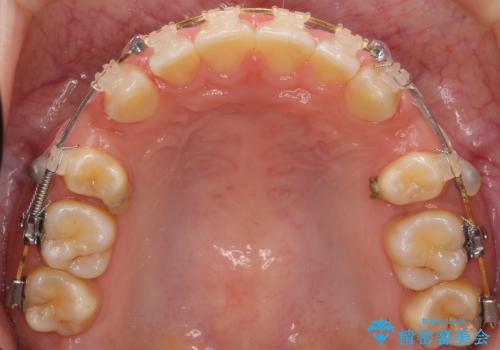

前歯のすきま 右上の小臼歯の垂直的骨吸収を抜歯で解決

- 審美装置

- 前歯のすきまを気にして来院。

奥歯が1歯対1歯で、過蓋咬合を呈していました。

レントゲンで、右上4番の近心の垂直的骨欠損があり、抜歯を行うこととしました。

short faceであり、結果上顎の臼歯を近心に大きくロスさせることになったたため、非常に長く治療期間はかかりました。